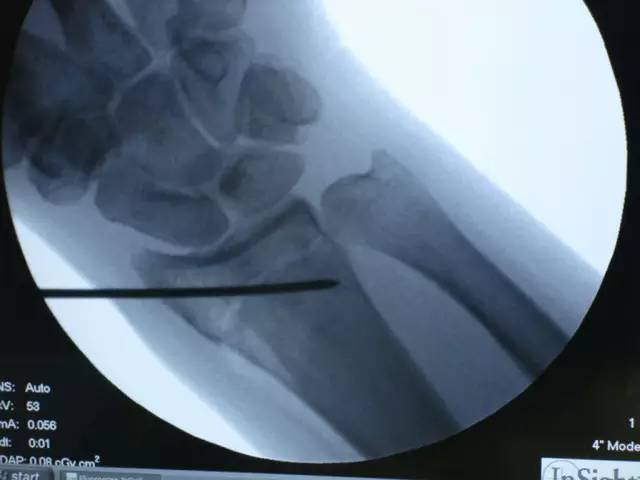

9. 术中 X 线影像证实,骨折最终获得解剖复位,钢板螺钉的位置满意:

钢板的位置非常重要,因为钢板不仅可以支撑骨折块,适当的位置还可以避免远端锁定螺钉侵入桡腕关节。术中仔细拍摄 X 线影像,投照方向与桡骨远端的掌倾角一致,可准确地观察桡骨远端桡侧的关节面,而术中先置入尺侧的螺钉也可更准确地观察桡侧的关节面。